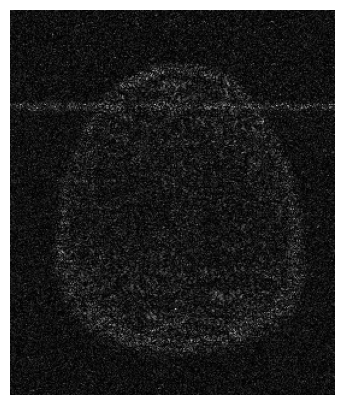

The visual inspection of the images reconstructed (available in Fig. 2) at acceleration factor 4 shows little to no visible difference with the ground truth original image. However, when increasing the acceleration factor to 8, we can see that smoothing starts to appear which leads to a loss of structure as can be seen in Fig. 3.

| T1 PSNR: 41.56 SSIM: 0.9506 | T2 PSNR: 40.68 SSIM: 0.9554 | FLAIR PSNR: 39.60 SSIM: 0.9321 | T1POST PSNR: 42.53 SSIM: 0.9683 |